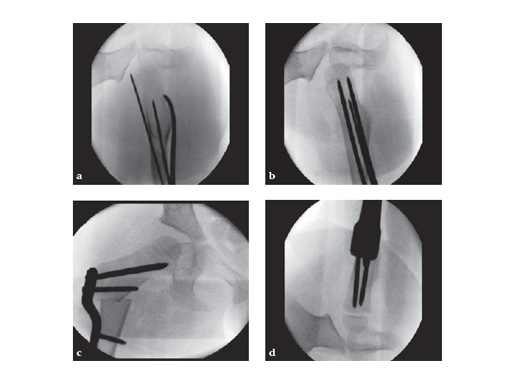

Intraoperative x-ray

Fig. 3-4